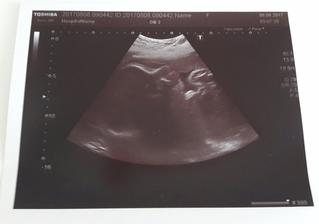

Náš zázrak 2017

Zázrak se snad stane skutečností...